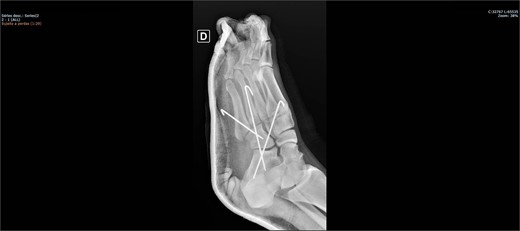

On physical examination, there was pain upon palpation over the dorso-lateral region of the midfoot, mild edema, hyperemia, inability to walk, and restricted ankle extension. Based on the physical examination, radiographs were requested. The examinations (Figs 1 and 2) showed inferomedial displacement of the cuboid bone without the presence of a fracture, diagnosing an isolated cuboid dislocation. He was immobilized and admitted for an open surgical reduction procedure.

The patient was placed on the surgical table in the supine position, anesthetized with spinal anesthesia, and given prophylactic antibiotic therapy with 2 g of cefazolin. After exsanguination of the lower limb, a dorsolateral incision was made on the foot over the cuboid bone and deepened through the layers until complete visualization of the cuboid bone was achieved. There was an interposition of ligamentous structures, such as the calcaneocuboid ligament, dorsal cuneocuboid ligament, and dorsal tarsometatarsal ligaments. After removing all structures that were interposed and preventing reduction, the cuboid was reduced easily, but instability was observed. Due to the instability found, percutaneous fixation was performed with three Kirschner wires: the first extending from the fourth metatarsal to the calcaneus, traversing the cuboid; the second from the fifth metatarsal to the cuboid; and the third from the cuboid to the calcaneus, from anterior-dorsal to posterior-plantar (Figs 3 and 4). After complete fixation, the stability of the cuboid was observed, maintaining it in the correct position, confirmed with fluoroscopy during surgery.